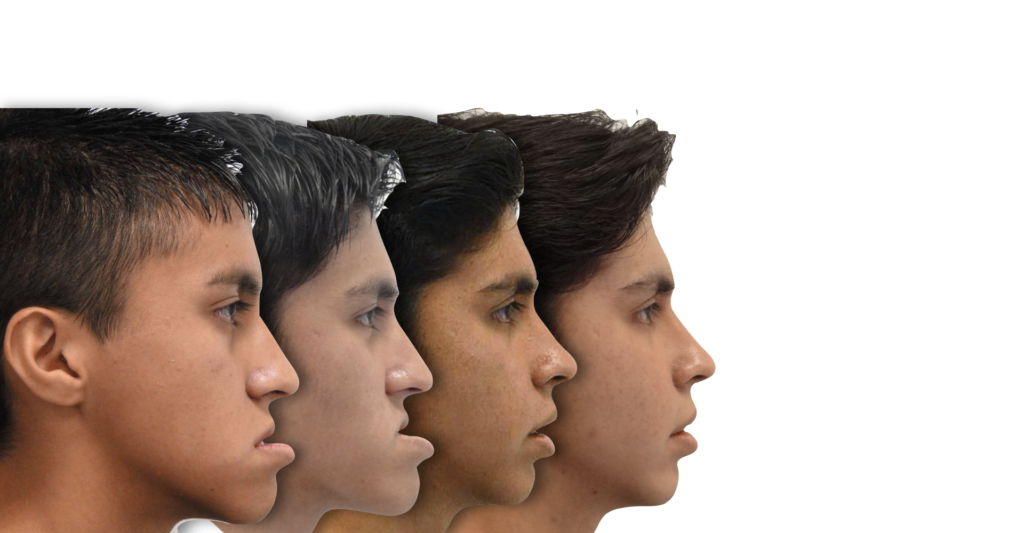

El siguiente caso clínico se trata de un paciente masculino de 18 años (al concluir su

tratamiento). Es un caso Orto/Quirúrgico complejo, donde el paciente presentaba una clase

ósea III debido a una hipoplasia maxilar y un aumento en la longitud del cuerpo mandibular,

ademas de presentar un biotipo dolicofacial (crecimiento de la cara hacia abajo). Este caso fue uno de los primeros casos quirúrgicos en concluir el Dr Quijada cuando aun era residente de la especialidad hospitalaria, donde hubo un trabajo en conjunto.

La primer fase que fue una expansión palatina y tracción de múltiples piezas incluidas en maxilar fue realizada por la Dra Scarlett Escobar, y posteriormente fue heredado el caso al Dr Francisco Quijada para su planeación y tratamiento Ortodóncico/Quirúrgico, una vez concluido la fase de Ortodoncia, estaba listo para la fase Quirúrgica, trabajando en conjunto con el servicio de Cirugía Maxilofacial, una vez concluida la cirugía el paciente estuvo listo para concluir su tratamiento y gozar de una fantástica mejoría en la estética facial, dental y una correcta función oral.

Paciente masculino con prognatismo mandibular severo y discrepancia esquelética Clase III. Presentaba mordida cruzada anterior, dificultad para masticar y alteración estética marcada. Se realizó tratamiento orto-quirúrgico con preparación ortodóncica y cirugía bimaxilar. El resultado final fue una oclusión funcional estable y una armonía facial significativa.

- Diagnóstico : Clase ósea III por hipoplasia maxilar

- Año : 2012